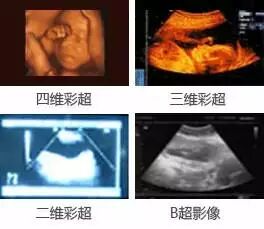

5D四维彩超与其他彩超的呈像区别

5D四维彩超在二维三维四维的基础上,更直观更清晰地呈现胎儿在宫内的动态图像,多方位多角度地观察宝宝的生长发育情况,还能够对孕妇潜藏的各类疾病进行精确检测。